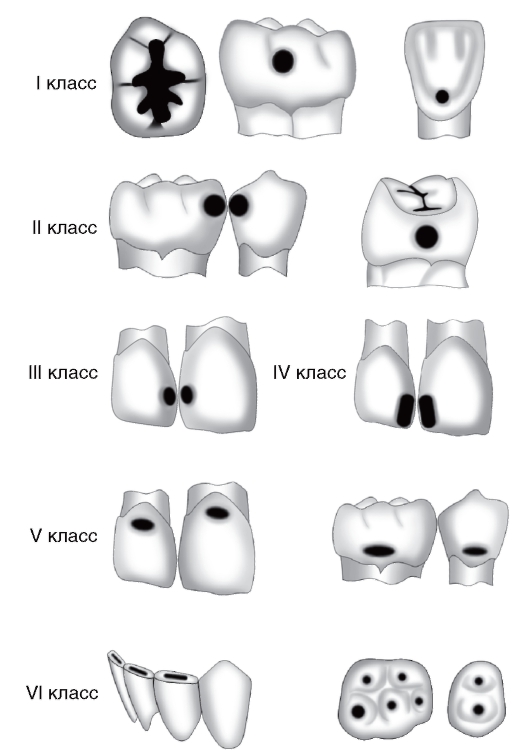

Препарирование кариозных полостей III класса: пошаговое руководство с фото